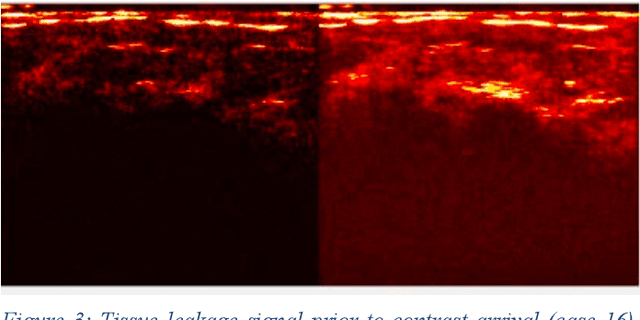

Molecularly targeted contrast enhanced ultrasound (mCEUS) is a clinically promising approach for early cancer detection through targeted imaging of VEGFR2 (KDR) receptors. We have developed computational enhancement techniques for mCEUS tailored to address the unique challenges of imaging contrast accumulation in humans. These techniques utilize dynamic analysis to distinguish molecularly bound contrast agent from other contrast-mode signal sources, enabling analysis of contrast agent accumulation to be performed during contrast bolus arrival when the signal due to molecular binding is strongest. Applied to the 18 human patient examinations of the first-in-human molecular ultrasound breast lesion study, computational enhancement improved the ability to differentiate between pathology-proven lesion and pathology-proven normal tissue in real-world human examination conditions that involved both patient and probe motion, with improvements in contrast ratio between lesion and normal tissue that in most cases exceed an order of magnitude (10x). Notably, computational enhancement eliminated a false positive result in which tissue leakage signal was misinterpreted by radiologists to be contrast agent accumulation.